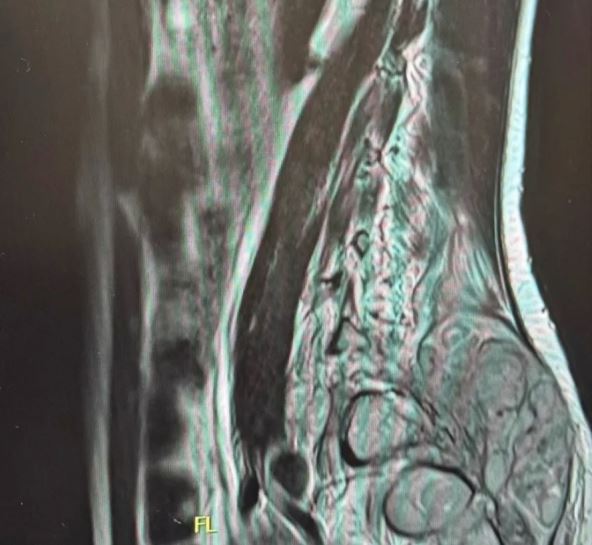

Onda se tokom 2023. godine, na njenim leđima pojavila tvrda, bolna izraslina veličine grejpfruta. Tada je njen dečko organizovao odlazak u Grčku na privatne preglede. Snimci su pokazali nepravilnosti, a nakon privatne konsultacije sa neurohirurgom, ustanovljeno je da Lea ima Evingov sarkom, redak i agresivan oblik raka kostiju i mekog tkiva.

Kada se pojavio tumor na leđima, Lea je dodatno smršala, izgubila snagu i morala da prekine studije i posao. Tek nakon privatnih snimanja i dodatnih konsultacija stigla je prava dijagnoza – Evingov sarkom.